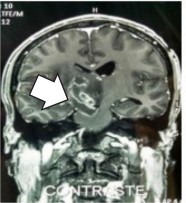

Se trata de un varón de 40 años, a quien se le diagnosticó VIH desde hace un año aproximadamente, sin tratamiento antirretroviral y sin controles. Acude al hospital al presentar ptosis palpebral derecha y un habla incoherente, después de 4 días aproximadamente, con dichos síntomas. En la evaluación se observa desorientación en tiempo, espacio y persona de manera intermitente, asimetría facial izquierda, hemiparesia izquierda 4/5, hiporreflexia izquierda ++/+++, sensibilidad disminuida en hemicuerpo izquierdo, signos meníngeos ausentes, III par craneal

pléjico, pupila derecha hiporreactiva a la luz 3,5 mm, falta de fluidez en el lenguaje y habla incoherente. Se toma resonancia magnética con contraste, donde se evidencia lesión compatible con toxoplasmosis cerebral (Figura 2); además, se realiza serología de LCR para toxoplasmosis cerebral mediante inmunoquimioluminiscencia (IMMULITE 2000), que detecta anticuerpos Ig M >1,1, con resultado “reactivo”, lo que indica una infección activa. Por tanto, recibe tratamiento protocolizado en la institución, y se evidencia restablecimiento; la evolución es favorable con mejoría de la sintomatología.

Figura 2 RMN de encéfalo contrastada. Se observa imagen captadora de contraste de 2-4 mm a nivel de mesencéfalo (flecha blanca).